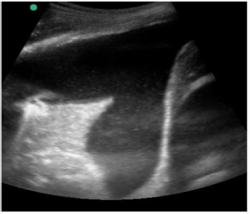

Caso clínico para responder à questão.

Um paciente de 50 anos de idade encontra-se, internado na UTI por conta de choque séptico de foco pulmonar, em ventilação mecânica na modalidade pressão e no modo assisto-controlado. Pela manhã foi submetido a acesso venoso central em veia axilar guiado por ultrassonografia. Ao exame físico, notou-se que o paciente está com hipotensão e taquicardia. A primeira hipótese diagnóstica é pneumotórax e é realizada radiografia com imagem apresentada.